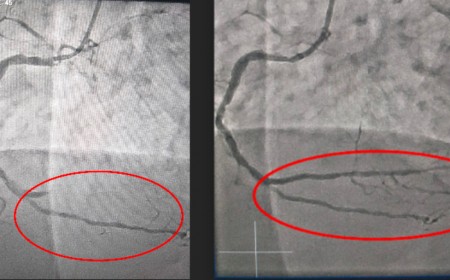

NGƯỜI PHỤ NỮ SUÝT CHẾT VÌ BỆNH NHỒI MÁU CƠ TIM

Người phụ nữ bị nhồi máu cơ tim cấp, 50 tuổi ngưng tim, ngưng thở, nhờ can thiệp kịp thời đã thoát cửa tử.